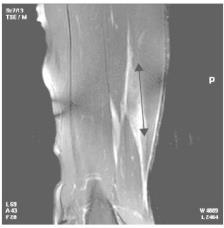

3.科研中一直使用传统临床诊断来确定腘绳肌损伤,近几年来影像学手段,特别是MRI的应用,颠覆了以前公认的典型临床征象:许多隐匿病例尽管临床征象不明显,但通过影像学诊断可以确定是腘绳肌损伤;有些病例虽然有典型的临床征象,但实际上只是不同病源的大腿后部疼痛,并不是腘绳肌损伤。

图三:腘绳肌拉伤后淤血青肿